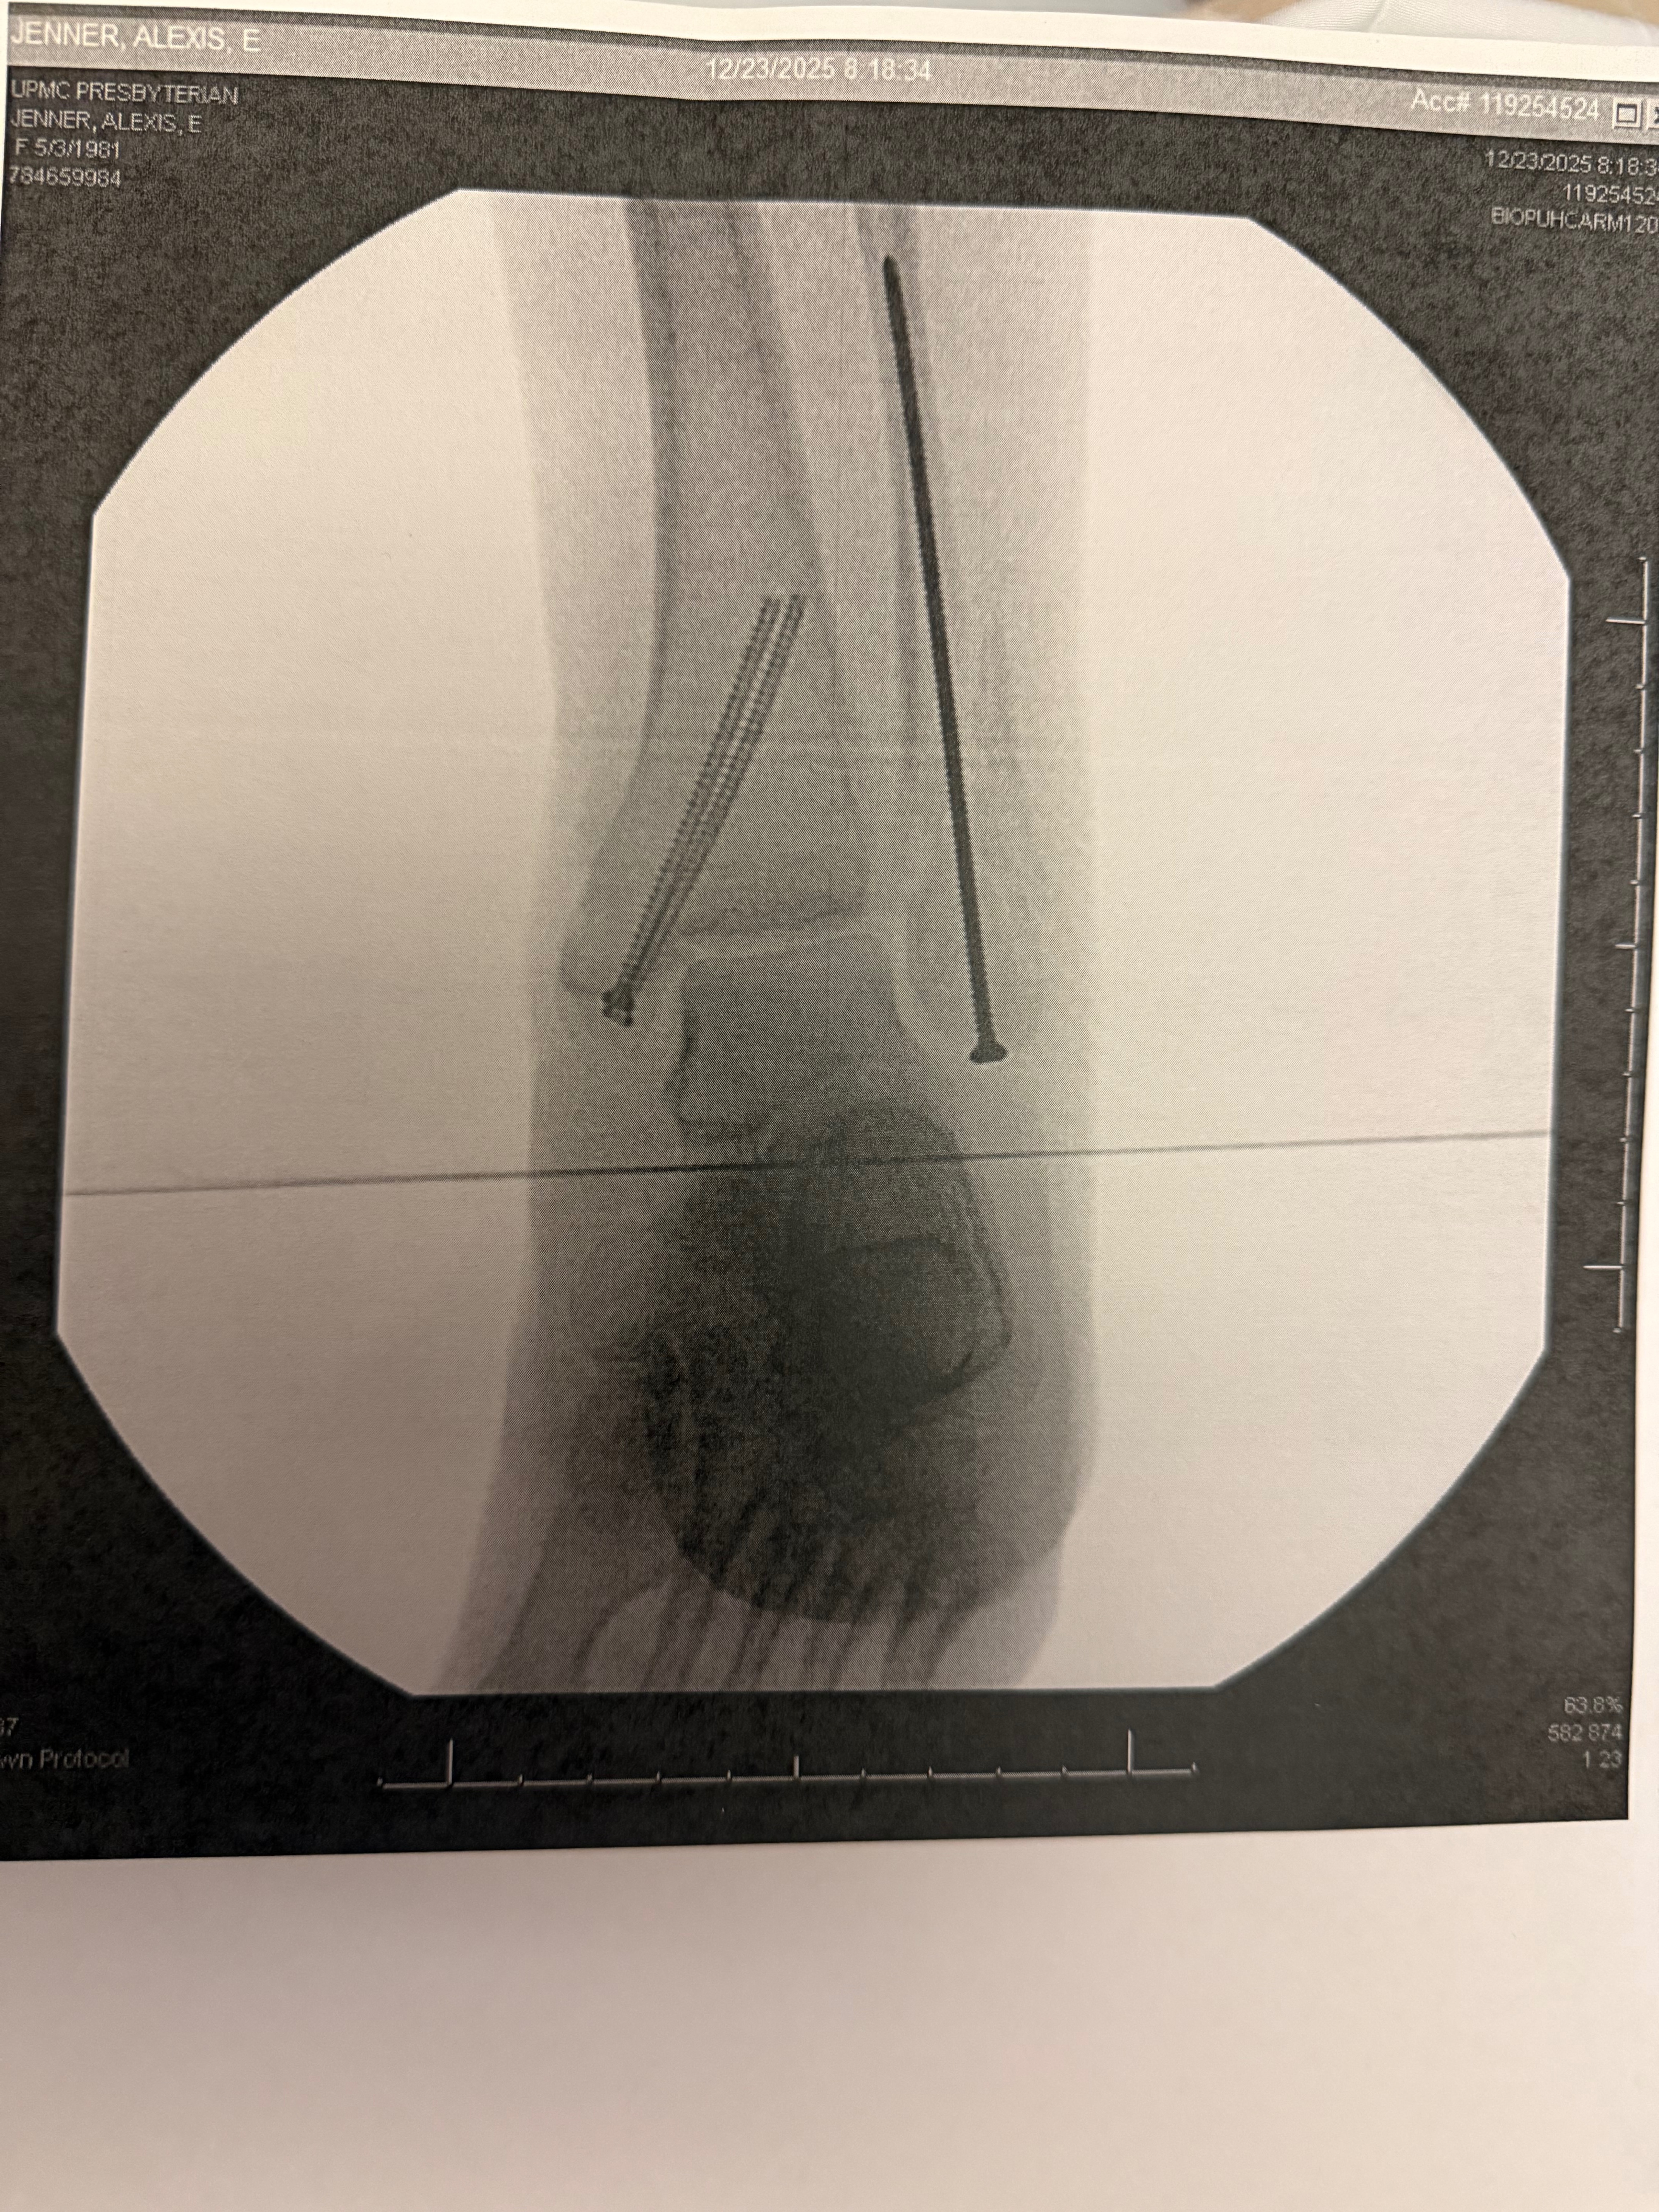

She recently completed her final chemotherapy treatment, which felt like a huge victory. Unfortunately, her journey took another unexpected turn. Due to bone weakness caused by cancer and treatment, she suffered a severe injury and broke her ankle in three places. She underwent surgery on Christmas Eve and now has a long recovery period, during which she is unable to work. While also having to continue her immunotherapy, which completely wipes her body out, and getting scans to make sure her cancer has not spread.